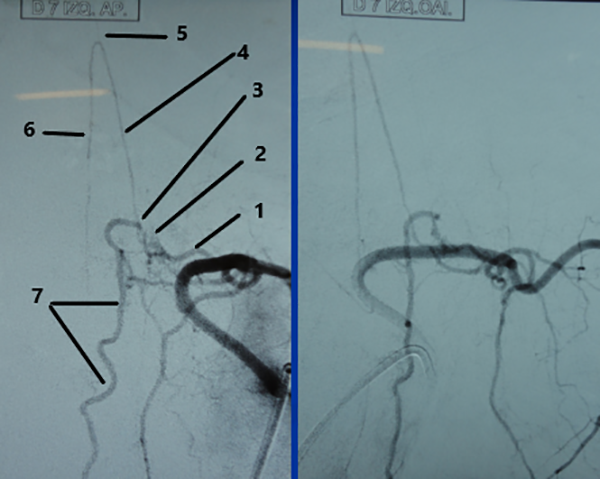

Figura 1: Irrigación segmentaria. (1) arterias segmentarias; (2) ramo anterior o ventral; (3) ramo posterior o dorsal; (4) ramo muscular; (5) tronco de la arteria radiculomedular con su ramo posterior (6) y anterior (7) haciendo la horquilla; (8) arteria espinal anterior; (9) arterias espinales posteriores y (10) ramo para el cuerpo vertebral.

Figura 10: Caso #2. ADM preoperatoria en AP y OAI. La misma arteria radiculomedular D 7 izq. (1) da origen a la arteria de Adamkiewicz (4) y a la FDAVE (2); pie de vena de drenaje (3); horquilla de la arteria de Adamkiewicz (5); arteria espinal anterior (6) y vena espinal posterior (7).